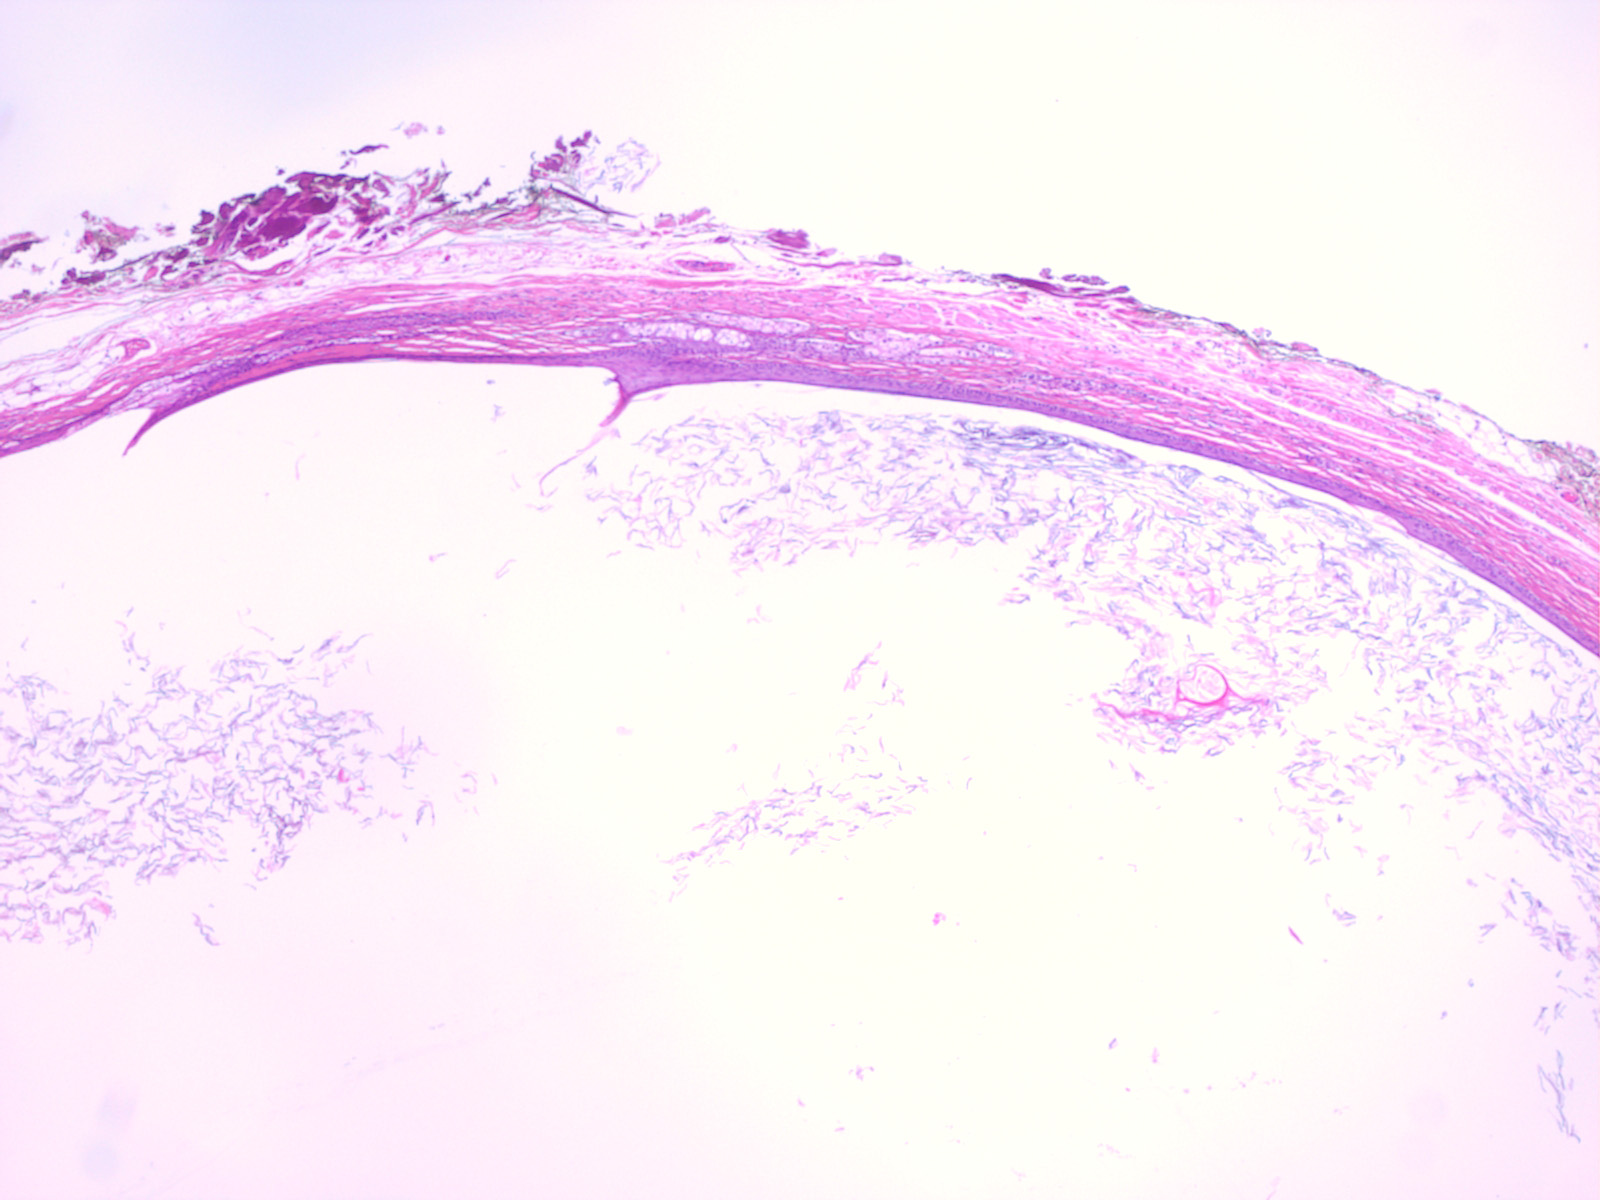

Histopathology. Dermoid cysts, in contrast to epidermal cysts, are lined by an epidermis that possesses various epidermal appendages that are usually fully matured . Hair follicles containing hairs that project into the lumen of the cyst are often present. In addition, the dermis of dermoid cysts usually contains sebaceous glands, often eccrine glands, ——–,. |